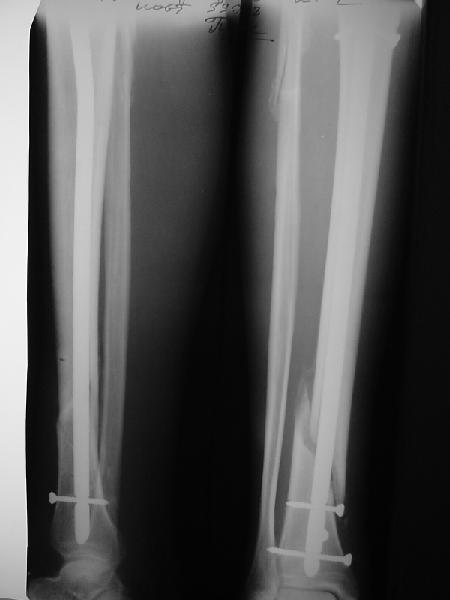

На мой взгляд, на снимках, приведённых Вами - неправильно сростающийся перелом дистальной трети большеберцовой кости, состояние после остеосинтеза интрамедуллярным гвоздём.

Как Вы пишите снимок под номером 1 - менсяц после операции, под номером 2- два месяца после операции.

Вы не послали послеоперационный снимок, поэтому трудно судить о состоянии редукции после операции.

I think that the X-Rays show S/P IMN of Spiral # of the Distal Tibia consoles in misalignment.

You wrote that a picture number 1 - f month after the surgery, and number 2-two months after the surgery.

You have not sent a postoperative X-Rays; so it's impossible to discuss about the condition of a reduction after operation.